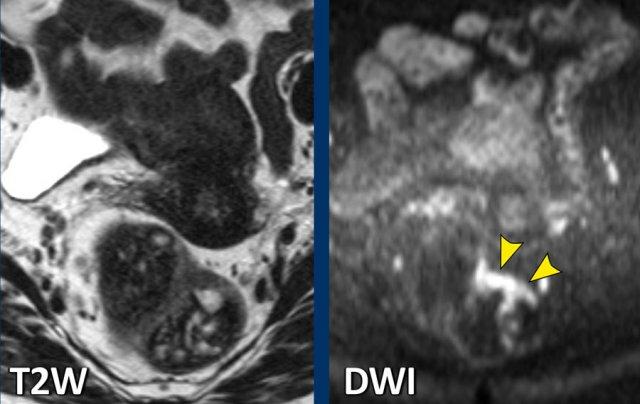

Vai trò của DWI trong việc phát hiện khối u còn sót lại

Hình ảnh khuếch tán (DWI) làm nổi bật mô có mật độ tế bào cao, nơi sự di chuyển của nước ngoại bào bị hạn chế.

Giá trị chính của nó nằm ở việc phát hiện khối u còn sót lại trong tình trạng dày thành xơ hóa khu trú (một phần dạng vòng nhẫn) tại vị trí khối u đã được điều trị.

Trong các trường hợp có khối u còn sót lại, tín hiệu cao thường được thấy ở bờ trong của mô xơ trên DWI giá trị b cao, với tín hiệu thấp tương ứng trên bản đồ ADC.

Đánh giá đáp ứng

Sau hóa xạ trị, các khối u trực tràng thường co nhỏ lại và trải qua quá trình biến đổi xơ hóa, biểu hiện dưới dạng giảm tín hiệu T2 rõ rệt tại vùng nền khối u.

Phân biệt xơ hóa với khối u còn sống sót vẫn còn là một thách thức.

Tín hiệu T2 không đồng nhất hoặc hiệu ứng khối tồn tại trong xơ hóa làm tăng nghi ngờ về bệnh còn sót lại.

DWI cải thiện đáng kể độ chính xác bằng cách phát hiện các vùng khuếch tán hạn chế trong xơ hóa.